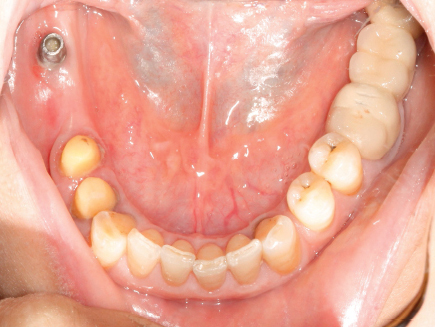

The framework was inserted in the patient's mouth and checked for accuracy and proper seating of crowns. The porcelain shade was then selected to match the remaining natural teeth. Then the porcelain was built on the splinted crowns. Semi–anatomical cross-linked acrylic teeth were set up, and the try-in was carried out. The saddle base was processed into heat cure acrylic resin, and the retentive nylon caps were inserted into the frame using the caps inserting tool. The splinted crowns-attachment assembly was finally cemented using Glassionmer cement (Fig. 6); the unilateral attachment prosthesis placement was then carried out (Fig. 7).

Fig. (6). Splinted crowns-attachment assembly was cemented.

Fig. (7). Attachmentretained partial denture.